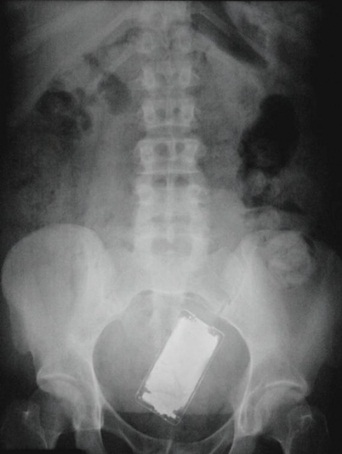

มาดูภาพเอกซเรย์ สารพัดสิ่งของที่เคยหลุดเข้าทวารหนัก

เผยภาพเอกซเรย์สุดอึ้ง สารพัดสิ่งที่เคยหลุดเข้าไปภายในทวารหนักผู้ป่วยทั่วโลก แปลกพิสดารกันจริง ๆ

การยัดสิ่งของต่าง ๆ เข้าไปในทวารหนักนั้น ไม่ว่าจะด้วยเหตุผลเพื่อหลบซ่อนการตรวจของเจ้าหน้าที่ทางการ หรือเป็นความผิดพลาดจากการแก้ขัดเมื่อเกิดอารมณ์ทางเพศก็ตาม สิ่งของที่หลุดเข้าไปนั้นล้วนแล้วแต่สร้างอันตรายให้กับอวัยวะภายในของผู้ป่วยได้หมด แต่ถึงจะเป็นอย่างนั้น เคสทางการแพทย์ว่าด้วยเรื่องของสิ่งแปลกปลอมที่หลุดเข้าไปในทวารหนักก็ยังมีให้เห็นอยู่เรื่อย ๆ ถมเถ แต่ละอย่างทำเอาอึ้ง ทึ่ง แบบไม่คิดว่ามันจะหลุดเข้าไปในทวารหนักได้จริง ๆ ดังเช่นตัวอย่างเคสที่เรานำมาฝากกันในวันนี้..

โทรศัพท์มือถือ